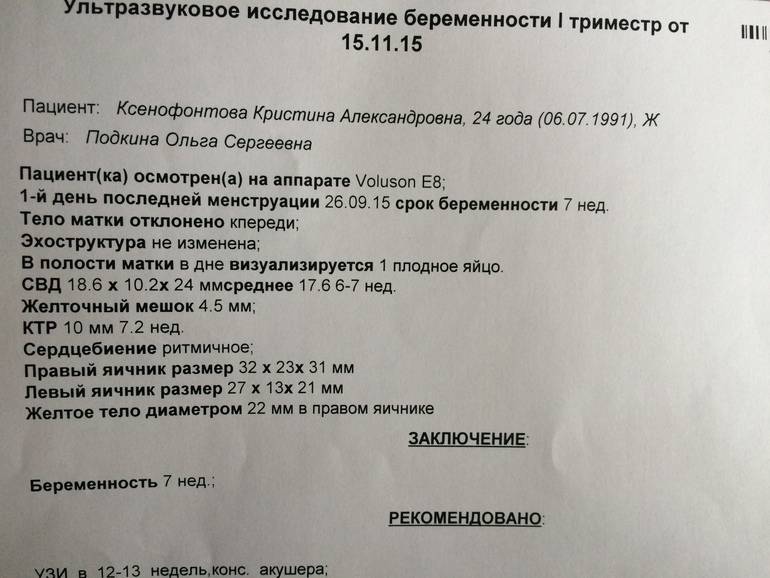

Фотографии на ранних этапах беременности

Раздел: Визуальный дайджест